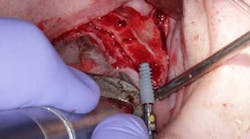

Surgery commenced. Implants on the lower arch were placed first (figures 7 and 8) and then we switched to the maxillary. The teeth were removed (figures 9 and 10) and the ridge was evened out (figures 11-13). The implants were aligned with the denture (figure 14) and then placed accordingly (figures 15-17). Healing caps were put on, and we were ready to start the restorative phase (figures 18-19).